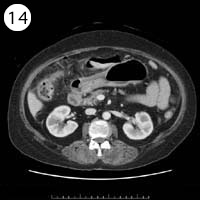

57歳 女性

単純CT

造影CT